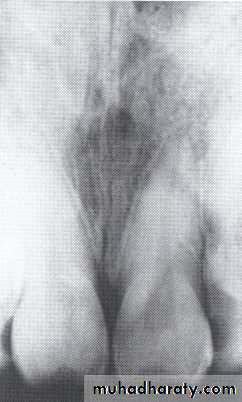

Concrescence of 7&8